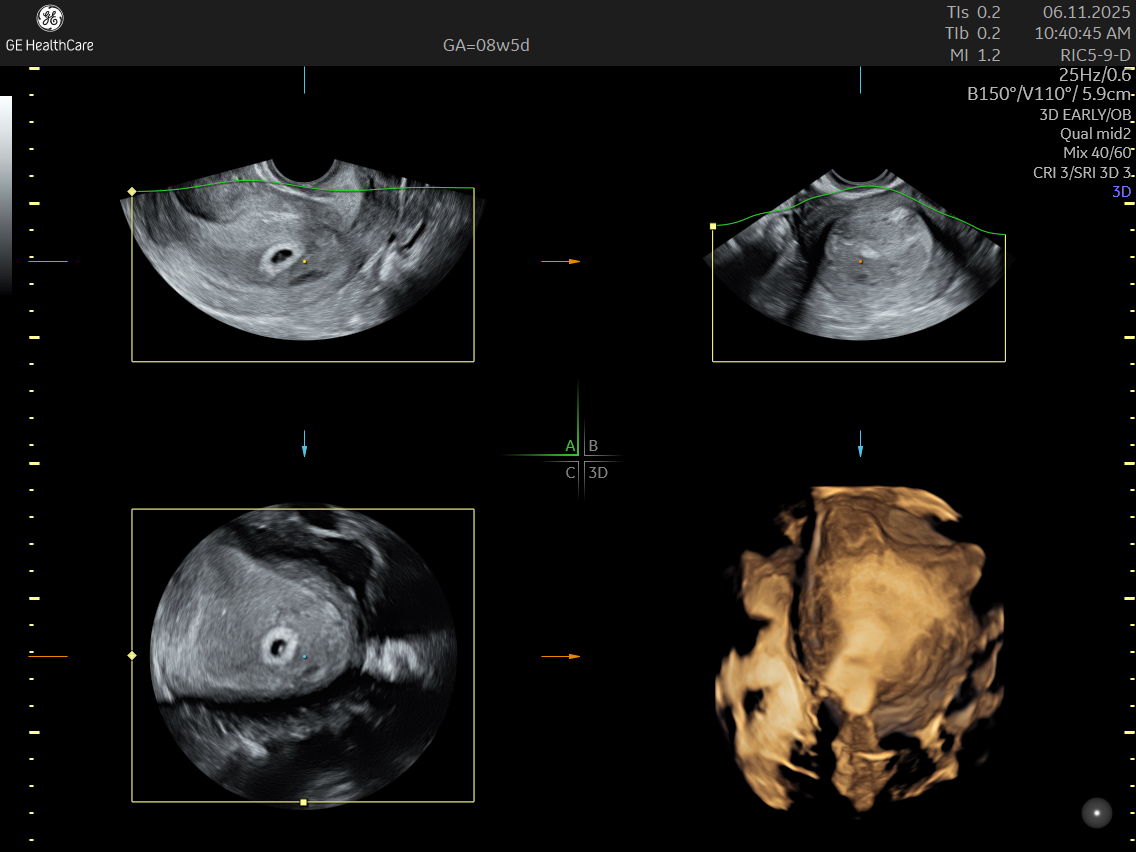

A Dating and Viability Scan is the first critical ultrasound in your pregnancy journey. Performed between 6 – 8 weeks, it confirms your pregnancy’s health, establishes how far along you are, and ensures an accurate start to your prenatal care.

- Usually conducted transvaginally for clear imaging

What Can The Scan Detect?